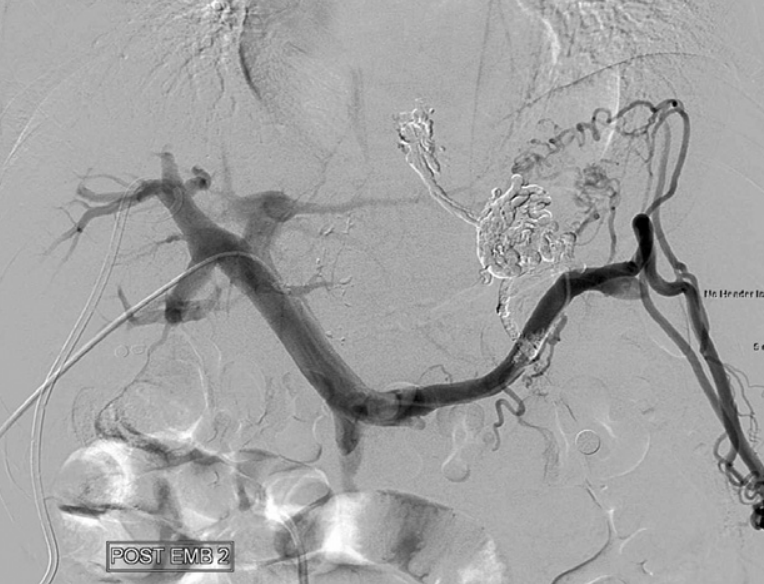

Fig. 6

Splenoportal venogram obtained immediately after glue embolization shows complete obli teration of the gastric varices and their inflow veins.